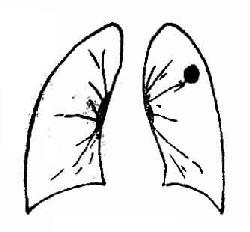

2.周围型肺癌(图3-31)又称肺野型,系指发生于肺段以下支气管直到细小支气管的肺癌。临床症状出现较晚。

周围型肺癌

图 3-31 周围型肺癌

X线表现:早期肿块较小,直径多在2cm以下,显示为密度较低、轮廓模糊的阴影,平片与炎症相似;但断层摄影可显示为球形致密影,轮廓较为清楚,边缘毛糙,有短毛刺。

癌肿继续发展,成为3cm以上较大的球形或圆形块影,平片显示密度较高,轮廓清楚,外形多呈分叶状,或有短小毛刺。有时表现为肺炎样小片状浸润,密度可不均匀。